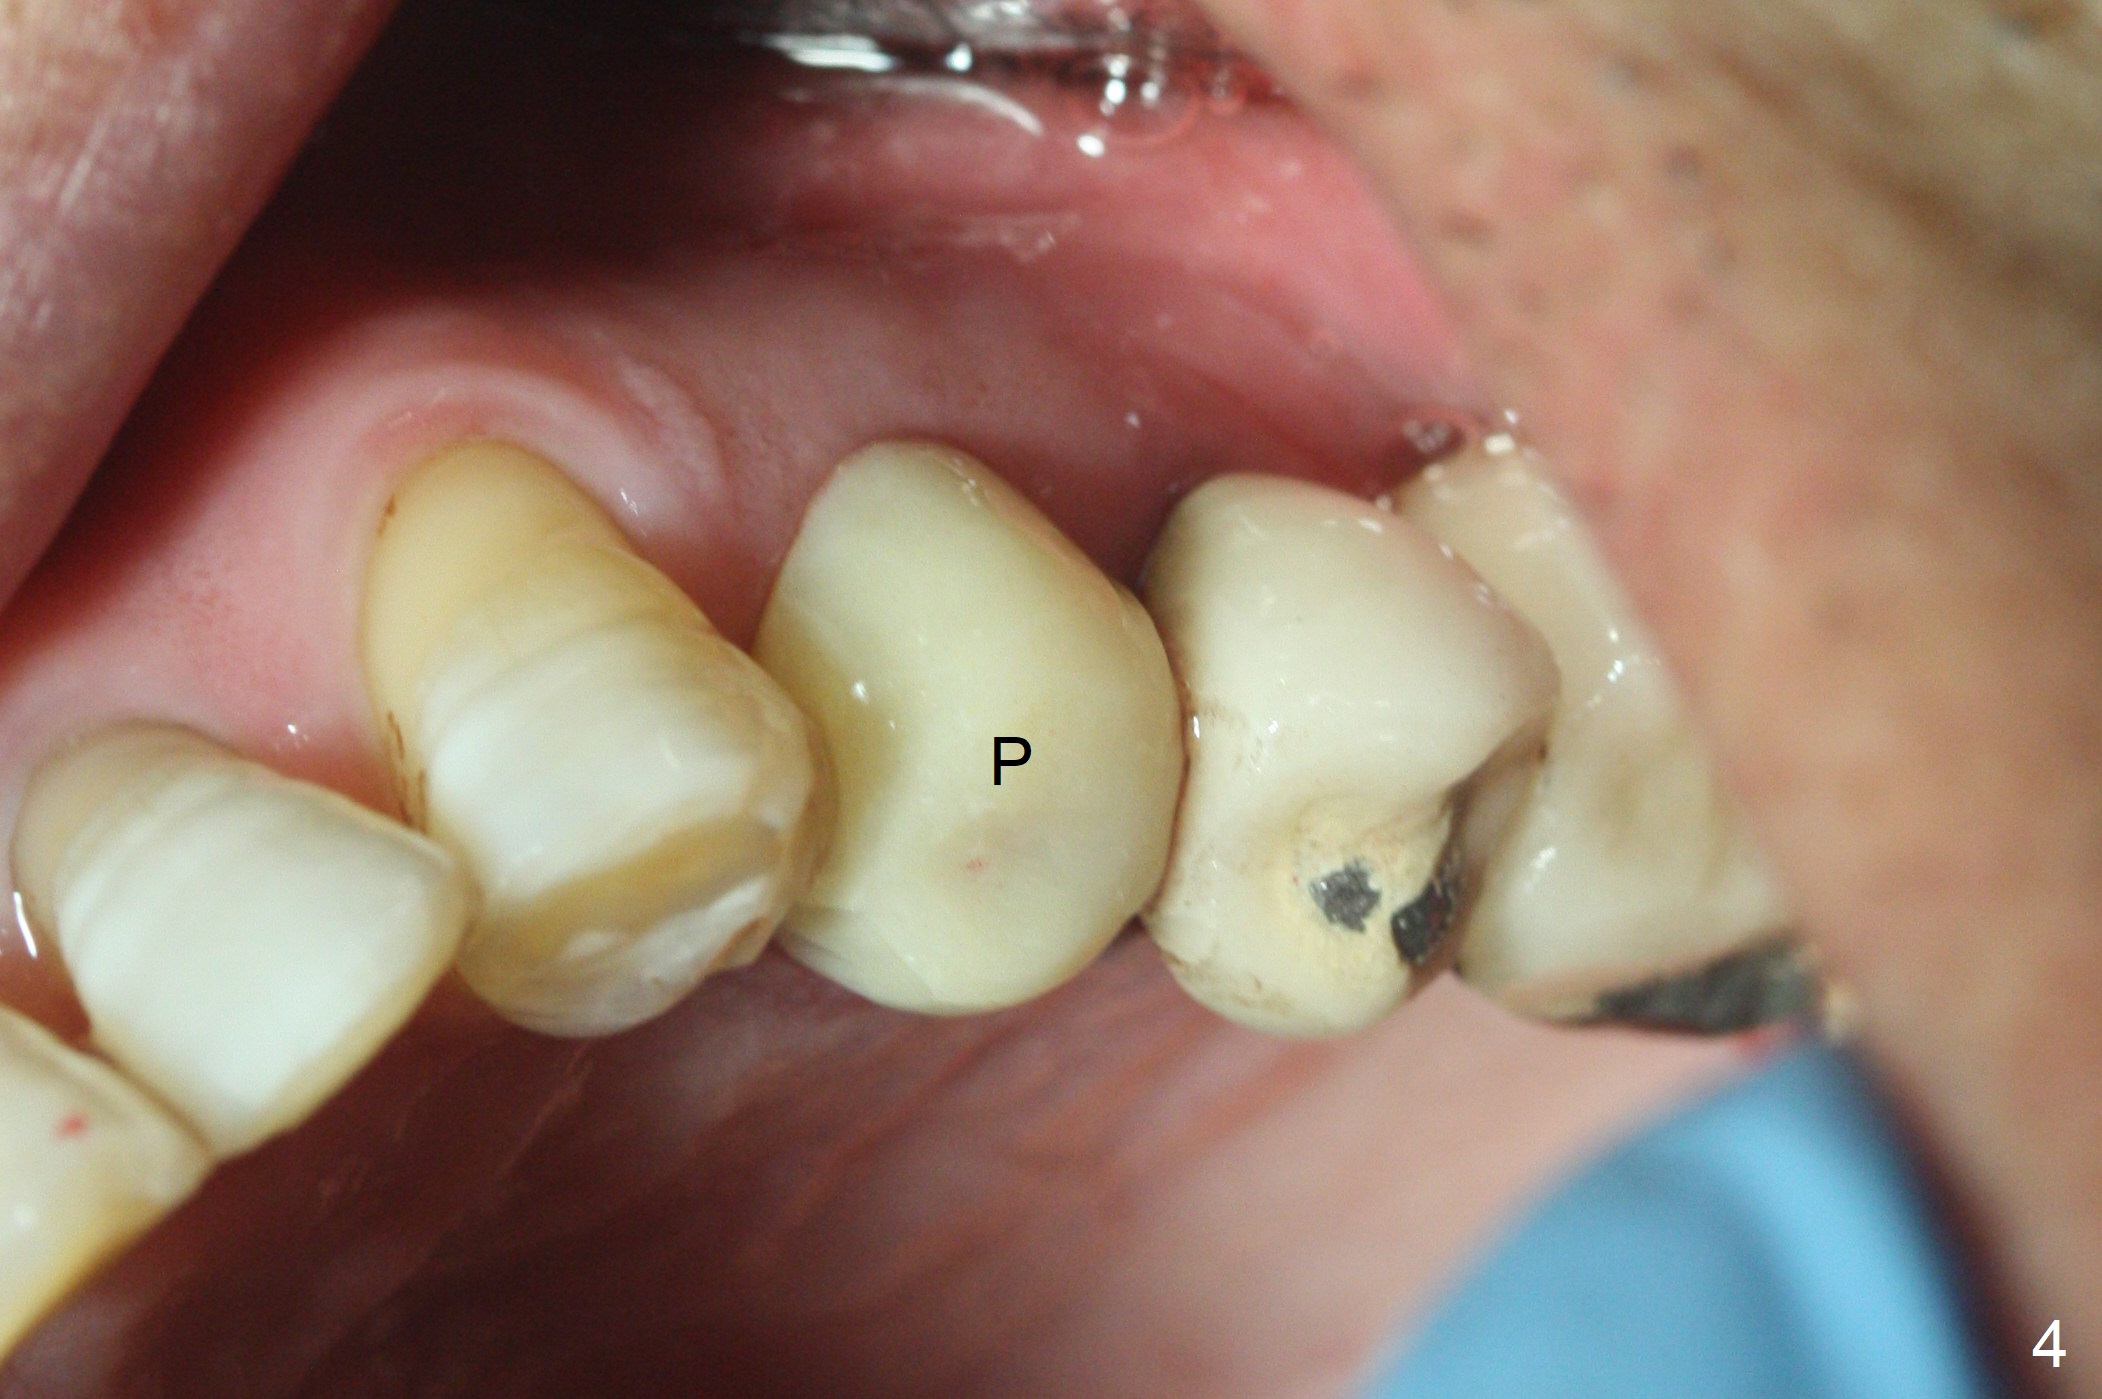

After extraction of the oval-shaped residual roots at #12 (Fig.1), osteotomy is initiated in the palatal socket for 18 mm; since the root of the canine curves distal (Fig.2 red dashed line), the osteotomy cannot afford to move mesial and extend more apical. A 3.8x15 mm implant is placed with > 50 Ncm (Fig.3). With immediate placement of a 4.5x4(3) mm abutment, an immediate provisional is fabricated to close the sockets (Fig.4 P). The provisional has clearance from the RPD clasps (Fig.5). In fact the implant could be longer, as shown by immediately postop panoramic X-ray (Fig.6). The implant seems to be osteointegrated 3 months postop (Fig.7). The tooth #13 is symptomatic with caries (Fig.8 C) 7 months post #12 crown cementation; the #13-15 FPD dislodges. The upper left quadrant is cold and hot sensitive 2.5 months post RCT (Fig.9); although there is mild percussion at #13, pulpal test shows that the tooth #15 has lingering pain. The FPD was recemented temporarily after RCT; it cannot be removed. The implant crown has been loose for several months during the pandemic before he returns 2 years 7 months post cementation. In fact the abutment has been not seated completely (from Fig.3 to 9). The crown/abutment is removed from the mouth; the crown is sectioned and separated from the abutment; the latter is reseated, but incompletely (Fig.10 <). With suspicion of the mesial crestal contact, profile drills 4.6 and 5.5 mm are used without effect. A new (old probably being worn) and longer (easy to turn in the narrow space) abutment is finally seated completely (Fig.11 (no gap)). After occlusal adjustment, abutment level impression is taken for a new crown.